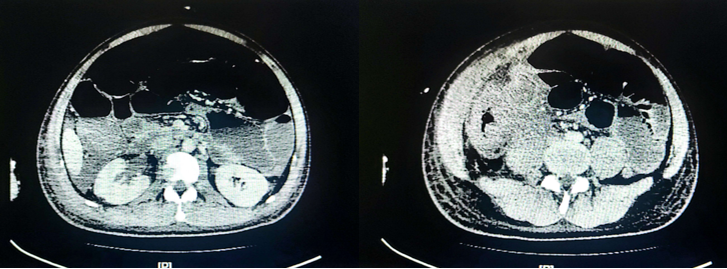

8月25日停用达托霉素,由于当时艾沙康唑暂时不可及,所以使用了两性霉素B胆固醇硫酸酯250 mg/d+亚胺培南抗感染。8月29日腹部MRI平扫+增强+弥散加权成像(DWI):右侧中下腹腔内(以右半结肠为中心)邻近前腹壁-腹膜后巨大边缘环形强化病灶,范围较前稍进展(图7),考虑升结肠缺血坏死,感染较前稍进展,并肠瘘可能。图7 腹部MRI平扫+增强+DWI(2022-08-29)第二次MDT(8月29日):血液科、感染科、普外科、消化科、麻醉科、营养科、临床药学科。MDT意见:患者目前有手术指征,但手术风险极高,预后极差,且费用高昂,继续积极抗感染治疗。患者体温36℃,腹胀腹痛较前稍缓解,可解少量大便,肠梗阻解除,生命体征平稳,转回血液科继续治疗。抗感染:哌拉西林他唑巴坦,两性霉素B胆固醇硫酸酯+艾沙康唑200 mg q8h(第3天开始200 mg qd)。9月2日, 患者体温36.7℃, 全腹胀痛好转, 右下腹皮肤溃烂黑痂, 范围约7 cm×8 cm, 局部破溃渗液(图8)。9月4日晚患者再次出现发热,体温38.3,将哌拉西林他唑巴坦改为亚胺培南+万古霉素抗感染。查血常规:白细胞13.12×109/L,中性粒细胞绝对值11.43×109/L;降钙素原3.57 ng/ml。分泌物细菌(真菌)培养:鲍曼不动杆菌(多重耐药)。9月5日腹部MRI平扫+增强+DWI: 右侧中下腹腔内(以右半结肠为中心)-邻近前腹壁-腹膜后巨大边缘环形强化病灶较前向外膨出、范围较前缩小(图9),考虑升结肠-邻近小肠及腹壁缺血坏死并感染, 肠瘘形成可能, 肠梗阻较前改善。图9 腹部MRI平扫+增强+DWI(2022-09-05)9月9日患者右下腹坏死物膨出,边缘进一步破溃,脱落,暴露腹腔内容物(图10)。在2019年ECMM发布的《毛霉病诊断和管理全球指南》中,指南小组强烈支持,除全身抗真菌治疗外,在可能的情况下,应尽早完成毛霉病的外科治疗。如有需要,应反复行切除或清创术。第三次MDT(9月9日):感染科、普外科、麻醉科、营养科、消化科、烧伤科、ICU、康复科。MDT意见考虑:患者有手术指征,但手术风险极高,需要多学科联合手术同时进行;尽快完善全腹部CT+腹部血管CTA,完善术前高风险谈话及手术/麻醉评估,患者及家属手术意愿强烈可考虑充分术前准备后手术。9月9日腹部CT+腹部血管CTA:肝中动脉瘤;腹主动脉+肠系膜上、下动脉+肾动脉CTA未见异常。9月10日行腹壁坏死组织切除+回肠部分切除+回肠造瘘+肠粘连松解术,术后转ICU观察。术中见:右下腹一13 cm×13 cm坏死腹壁与肠管组织,与周围组织无粘连,予以取出,回盲部、部分乙状结肠、右侧上段输尿管包裹在腹壁坏死组织中(图11)。病理组织活检:骨骼肌及肠壁可见大量真菌菌丝、孢子及细菌菌团,且部分真菌菌丝及孢子似位于脉管内,倾向侵袭性真菌病并广泛播散;见阑尾组织显著急性坏疽性阑尾炎,阑尾管壁及管腔内见真菌菌丝及孢子。9月14日患者生命体征平稳,无发热,为求坏死腹壁修复,转入烧伤科继续治疗。9月15日患者生命体征平稳,胆仍有腹痛、腹胀,转入胃肠外科治疗,后续进食半流质,腹痛缓解,造瘘处有排便排气。术后持续予以两性霉素B胆固醇硫酸酯+艾沙康唑治疗。9月20日腹部增强CT示(图12):“腹壁坏死组织切除+回肠部分切除+回肠造瘘+肠粘连松解术”术后改变,右中下腹术区少量渗出、积液;左侧回肠造瘘口近端小肠积液、积气扩张;右侧输尿管上段继发右肾及输尿管上端轻度积水同前;盆腹腔脓肿较前吸收。肠腔内高密度影,造影剂残留?肝中动脉动脉瘤较前增大。肝脏多发低密度灶同前,仍考虑小脓肿形成可能。9月22日,患者生命体征平稳,复查骨髓形态及流式均未见异常细胞。11月1日,烧伤整形科于全麻下行"右腹壁腹膜补片修补+腹壁缺损右股前外侧皮瓣转移修复术"。术前已停用两性霉素B,予以艾沙康唑口服维持治疗。2024年1月3日随访腹部CT提示患者恢复较好(图13)。